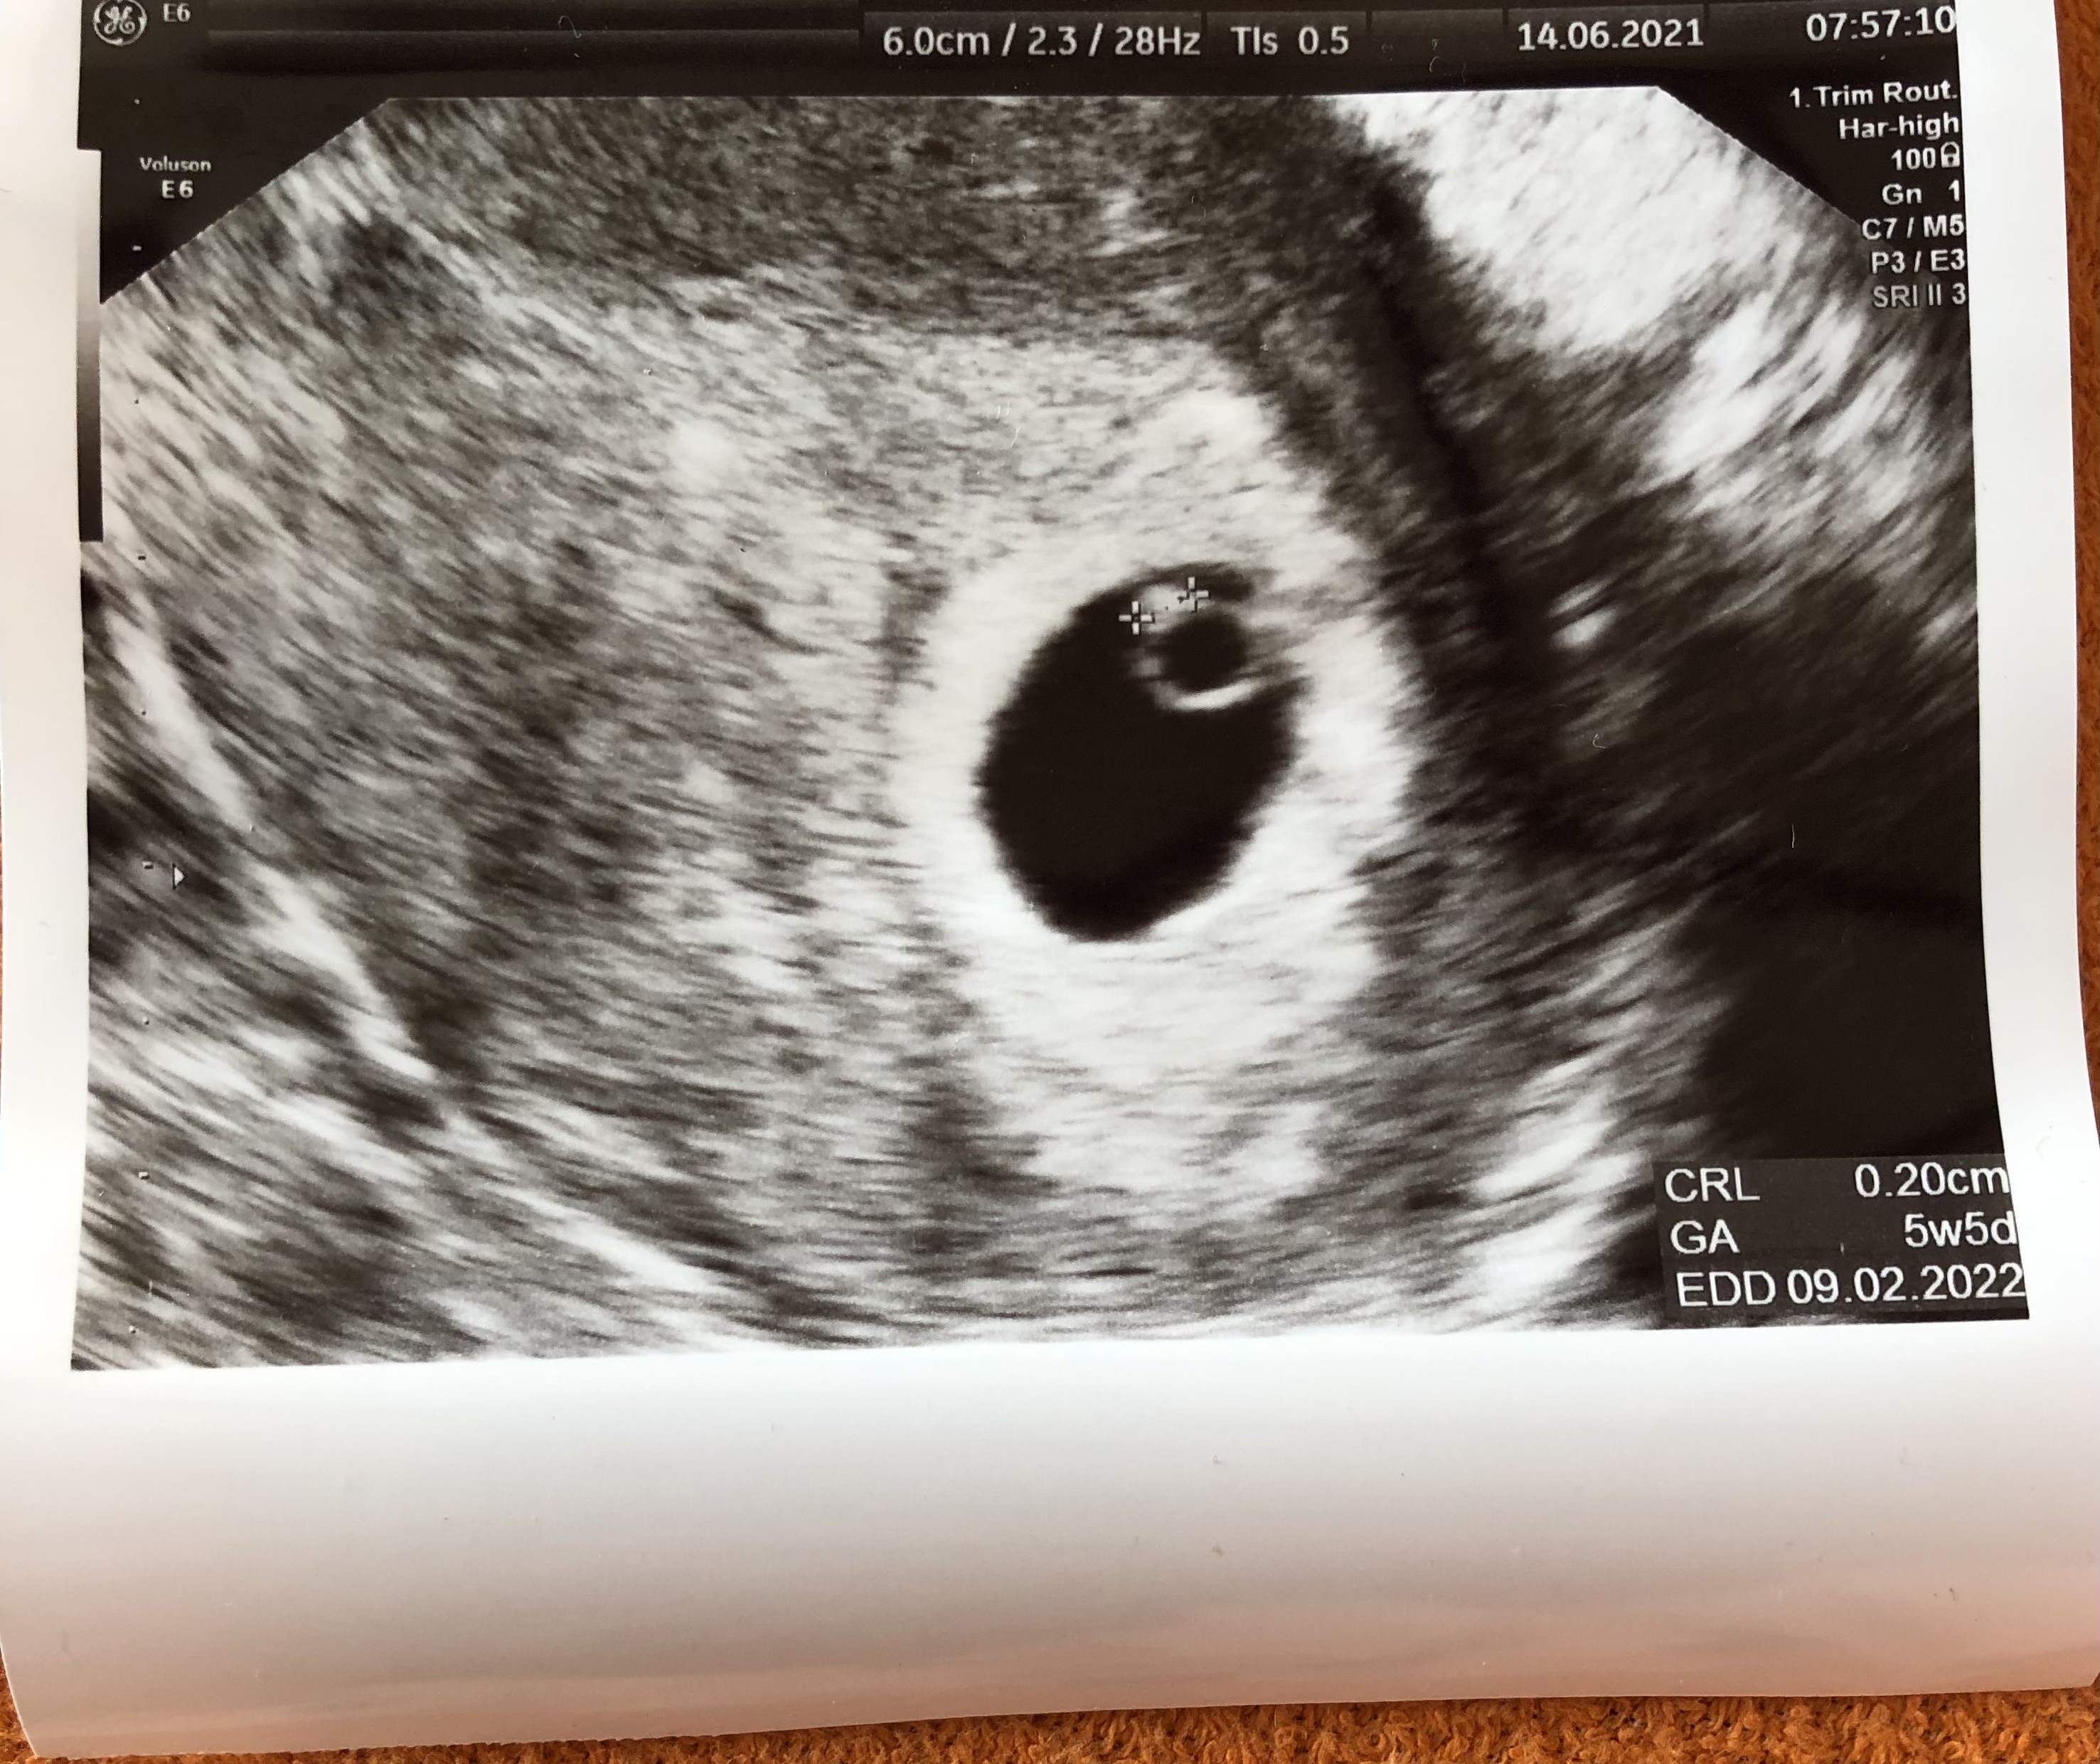

Dlatego teraz byłam gdzie indziej, u cudownej pani doktór którą też ma podejrzenie pustego jaja niestety ale nie przekreśliła mnie z góry , po prostu powiedziała żebym się nie stresowała może późno fasolka kiełkuje i na następnej wizycie ja zobaczymy wraz z serduchem

kazała powtórzyć bthcg ale doszłam do wniosku że nie robię , będzie to dla mnie dodatkowy stres, więc po prostu na spokojnie czekam do piątku